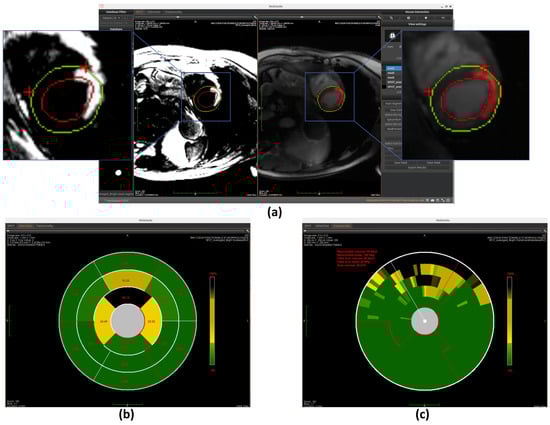

Similarly to the automated segmentation function, this model is implemented using the ONNX Runtime library to optimize inference performance within the workspace. The final detection results are displayed on BR-LGE images (shown in Figure 10a), enabling simultaneous comparison with scar visualization in corresponding BL-LGE images.

Once the segments are accurately divided, the model calculates the scar area as a percentage of the total area within each segment. This is done by measuring the number of pixels corresponding to the scar in each segment and dividing it by the total number of pixels in that segment. These percentage values are then mapped to the corresponding positions on the bullseye plot, visually representing the spatial distribution of myocardial scars, as shown in Figure 7b, Figure 10b, and Figure 11b.

Once the segmentation is established, the model quantifies transmurality by assessing the proportion of scar tissue along each chord. For each chord, the ratio of scar thickness to the total myocardial wall thickness along the corresponding radial path is computed, reflecting the extent of myocardial wall affected. These transmurality values are then visualized in the bullseye plot, offering a high-resolution visualization of scar depth throughout the myocardium, as shown in Figure 7c, Figure 10c, and Figure 11c.

Figure 10. Overview of scar detection using the U-Net model. (a) Detected myocardial scar visualized on the BR-LGE image—highlighted as the red region between the left ventricular endocardium (red circle) and the epicardium (green circle), alongside comparison with the corresponding BL-LGE image. (b) Infarct size visualization using an AHA 16-segment bullseye model. (c) Transmurality evaluation presented with a bullseye plot composed of 100 equally spaced chords.